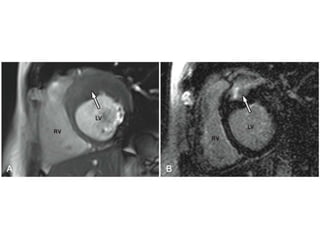

• #74 A, Patient with hypertrophic cardiomyopathy with severe panseptal hypertrophy (arrow). B, The septum demonstrates dense LGE (arrow) consistent with fibrosis